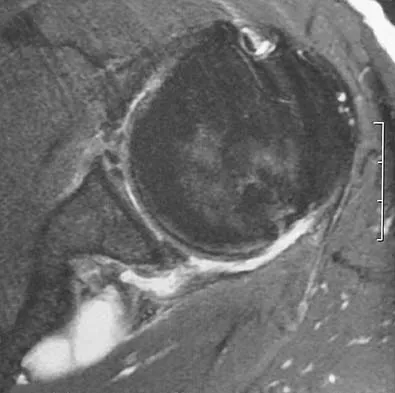

Question 49

A 54-year man has left shoulder pain and weakness after falling while skiing 4 months ago. Examination reveals full range of motion passively, but he has a positive abdominal compression test and weakness with the lift-off test. External rotation strength with the arm at the side and strength with the arm abducted and internally rotated are normal. MRI scans are shown in Figures 1a and 1b. Treatment should consist of

Explanation